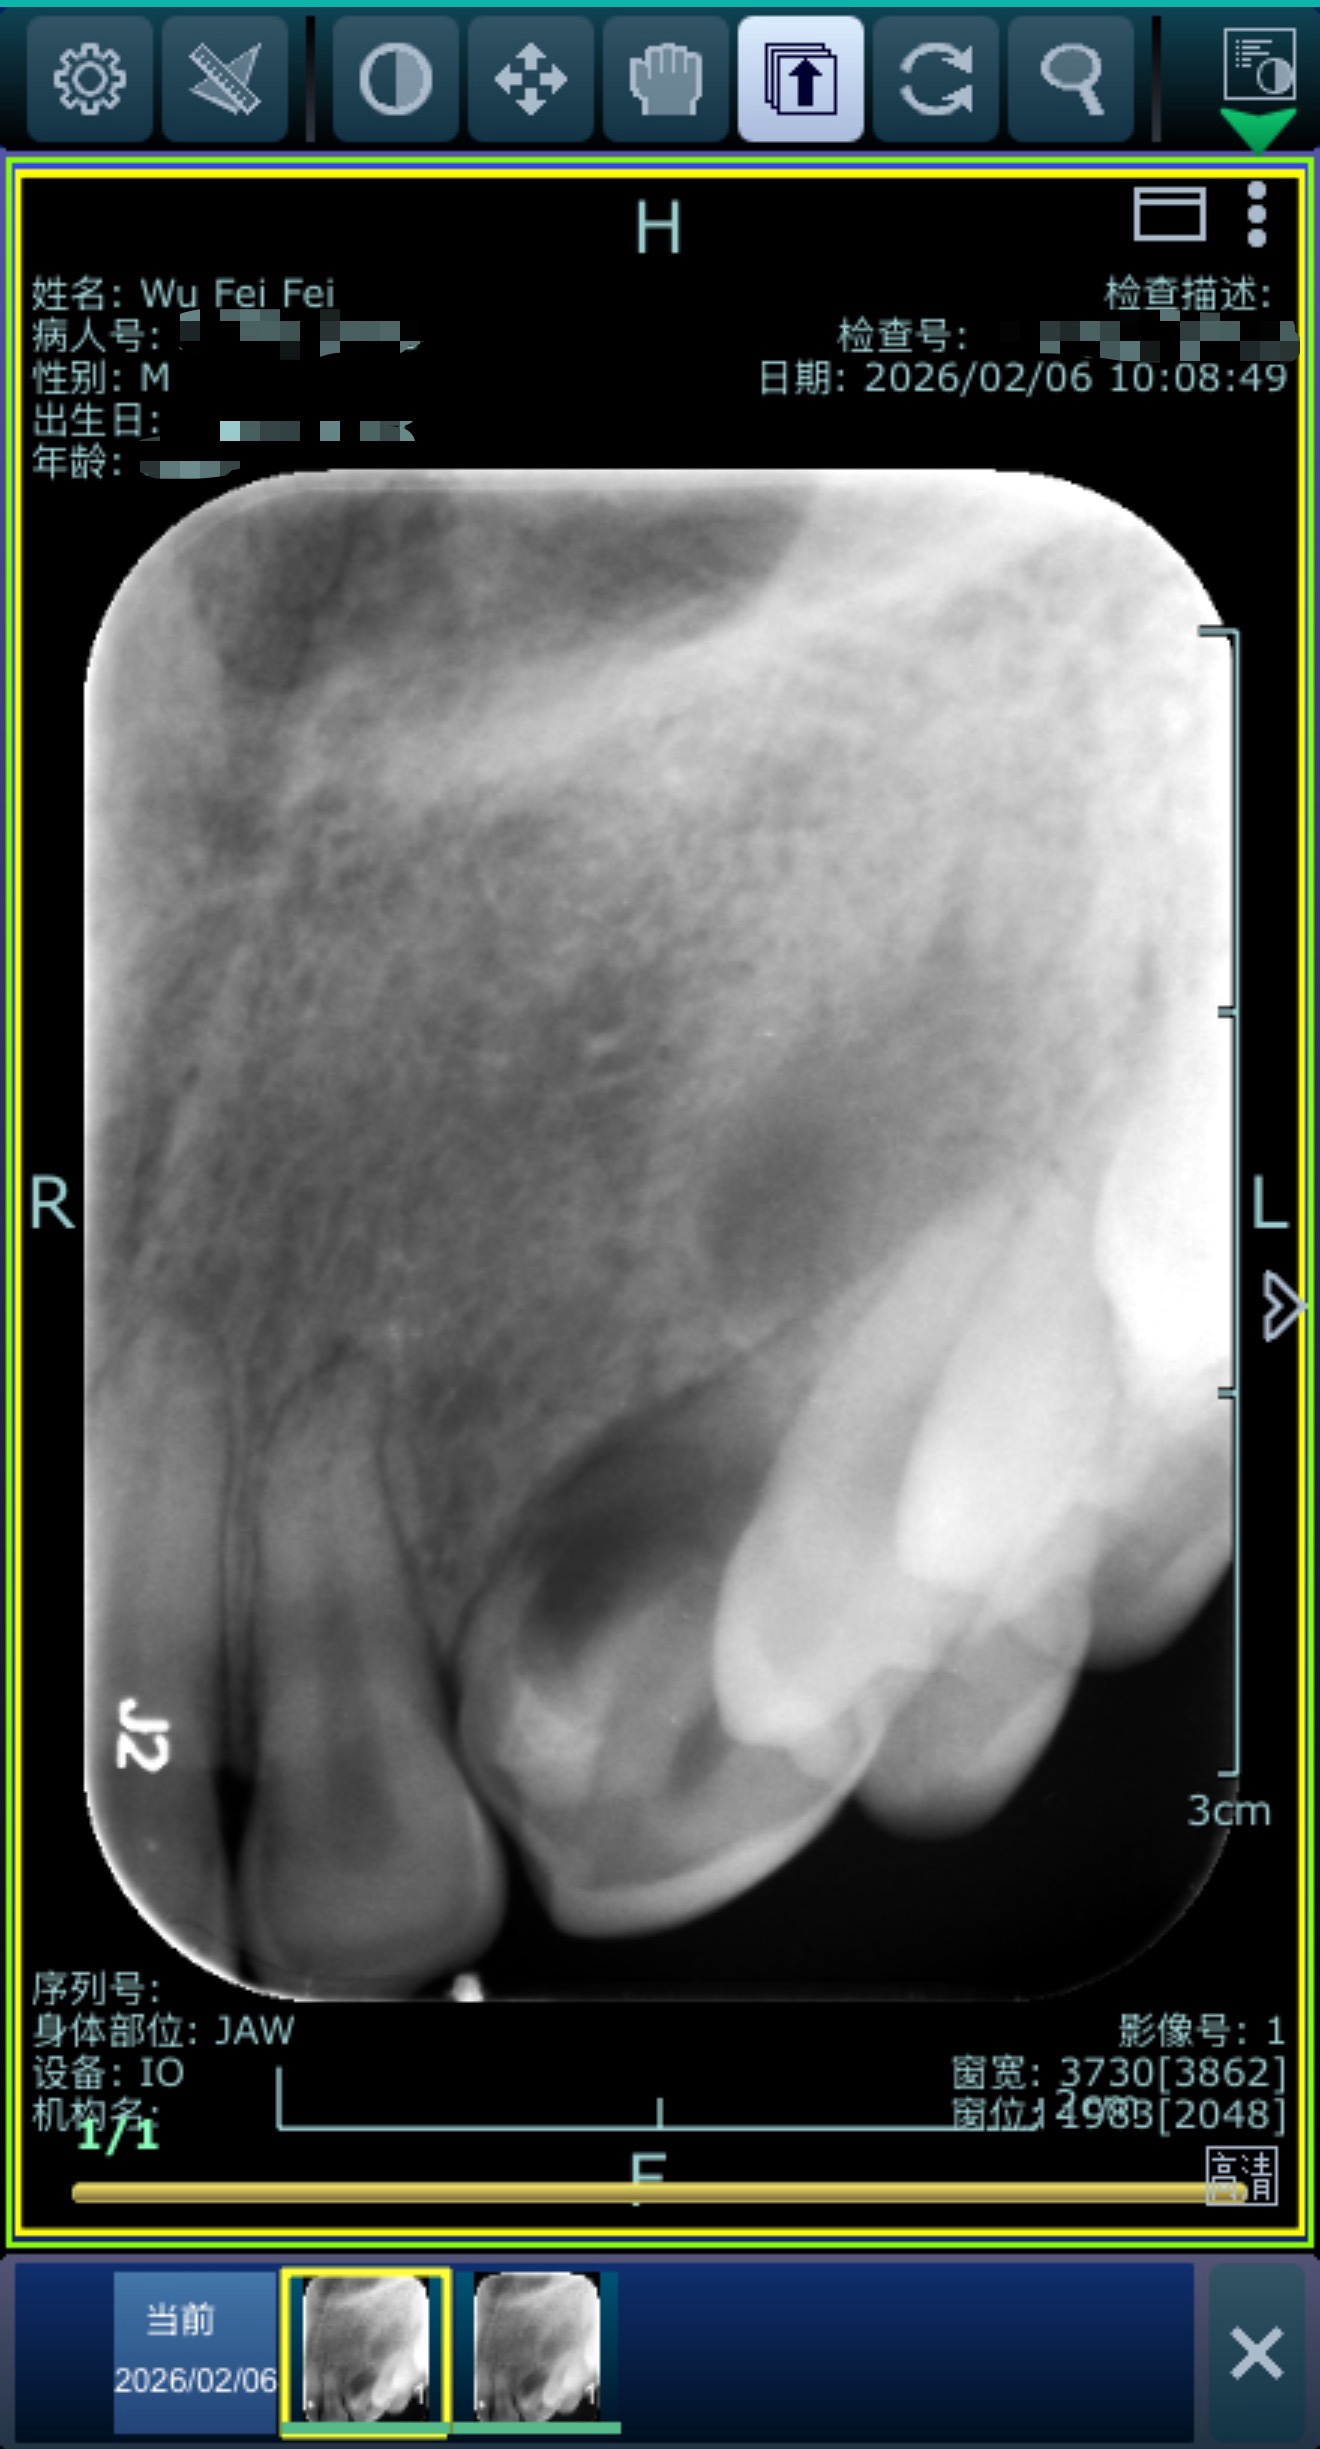

上午请假,去医院看牙。去年洗牙时,说我左上这颗尖牙表面颜色有点怪,让我拍片检查下,当时因为备孕中没有继续。今天约了浙一主任专家,拍了片子,诊断为龋齿。说这颗牙长的很歪,里面还烂了一部分,清理后牙龈一直在出血,之前这部分一直有炎症,让我下周五再去补下,今天补可能补不牢。挂号150,牙片才15。后续每天早晚刷牙,每年洗牙。